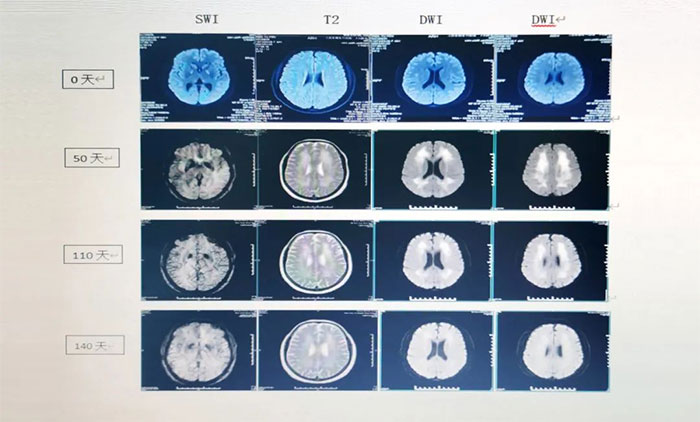

▲ 患者影像變化

經(jīng)過會(huì)診,張靜波主任團(tuán)隊(duì)制定了完善的治療方案,給予靶向藥物托珠單抗及地塞米松治療,同時(shí)予繼續(xù)對(duì)癥及支持治療,以及高壓氧、經(jīng)顱磁刺激等治療。經(jīng)上述治療兩個(gè)月后,患者病情明顯好轉(zhuǎn),神志清晰,行走自如,可以正常與人交流,大小便也恢復(fù)正常,目前已經(jīng)康復(fù)出院。